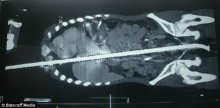

Fémrúd szúrta át a fiú testét